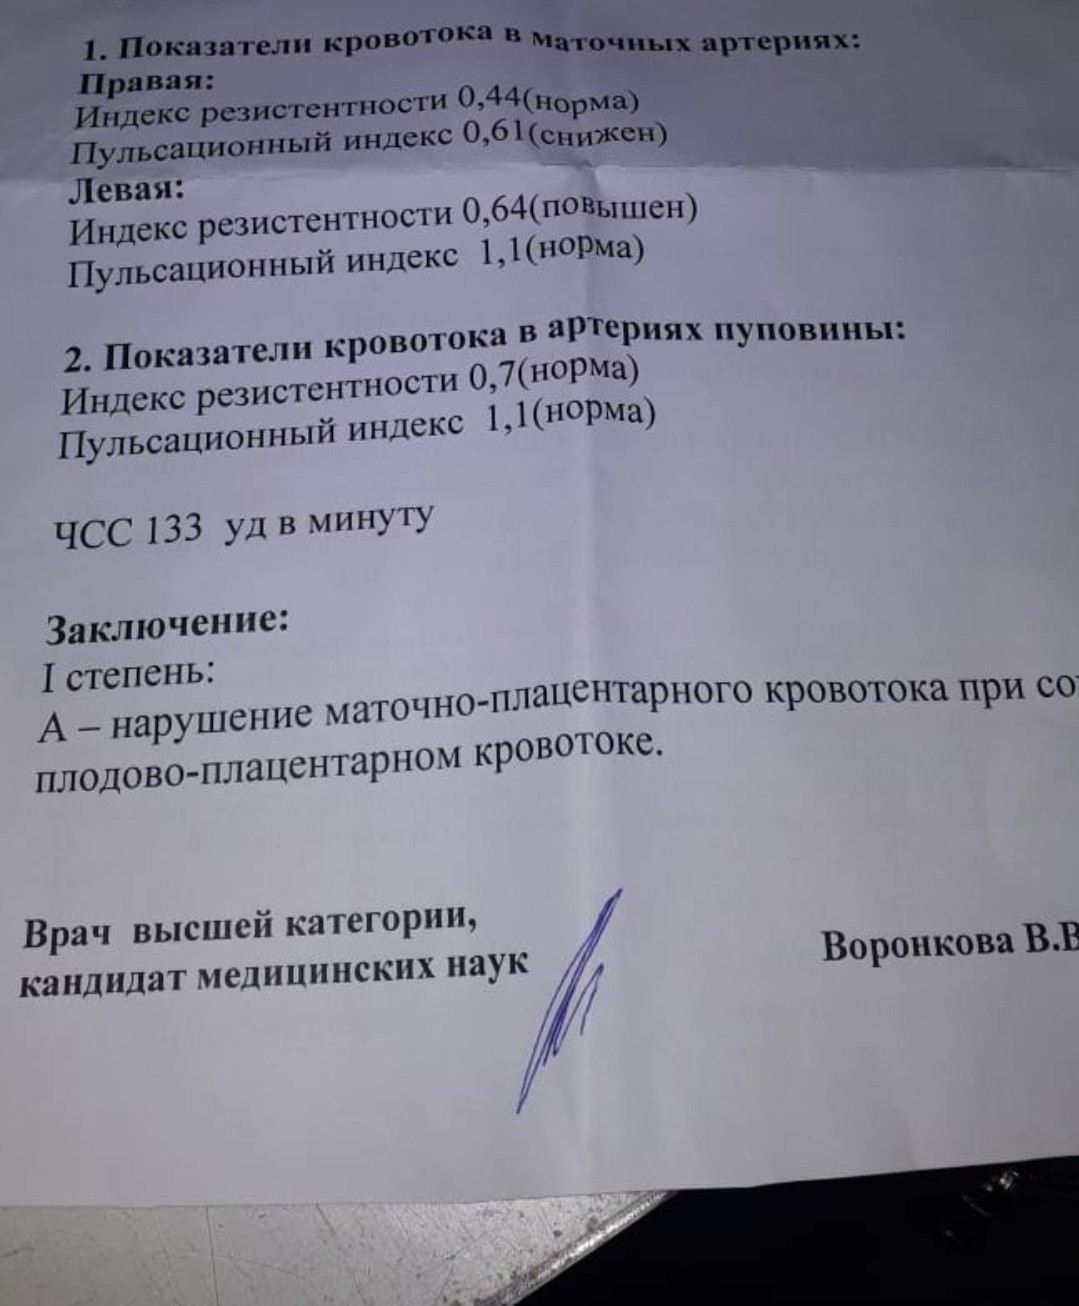

Особенности и диагностика левостороннего кровотока